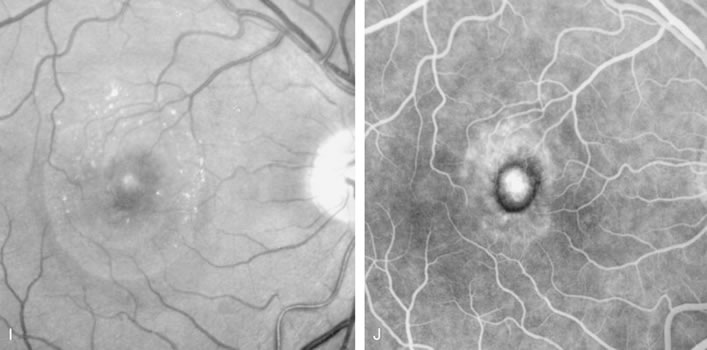

DIAGNOSIS Central serous chorioretinopathy (CSC) is characterized by breakdown of the outer retinal barrier, with leakage of fluid through a defect in the retinal pigment epithelium into the subretinal space, resulting in a serous neurosensory detachment.78–205 The ophthalmologist can usually diagnose CSC based on the clinical examination and demographic information.93–95 Most patients with CSC are middle-aged men74 who often have type A personalities.75, 96–104 CSC has also been associated to the use of corticosteroids,105–118 pregnancy,119–126 increased adrenaline level and stress,127–132 hemodialysis,133,134 collagen vascular diseases,135–147 and hypertension.148–157 CSC typically presents as a large serous detachment in the posterior pole without an obvious source of the subretinal fluid.76 However, because a small CNV cannot be ruled out, FA is usually done to confirm the diagnosis. Characteristically, there is a small RPE defect, which hyperfluoresces early, and then there is slow filling of the overlying neurosensory detachment, which may have a classic “smokestack” (Fig. 21) or “ink blot” (Fig. 22) appearance.158–161 Occasionally, FA demonstrates multiple sites of leakage (Figs. 23, 24, and 25). FA sometimes fails to distinguish CSC from CNV readily because fibrinous subretinal precipitates can cause slow filling of the RPE detachment, which is suggestive of CNV (Fig. 26). Sometimes peripapillary PCV can cause a neurosensory macular detachment masquerading as CSC (Fig. 27).77

The diagnosis of CSC may be difficult if there is neither RPE detachment nor evidence of leakage into the subretinal space. Possible causes of a neurosensory elevation without evidence of leakage in the macula include CSC with the RPE detachment located outside the macular area (Fig. 28), CSC with a healed leak (in which case the neurosensory detachment should resolve soon), peripheral retinal hole, choroidal tumor, congenital optic nerve pit, and idiopathic uveal effusion syndrome. There are several other considerations in a patient who presents with a localized serous detachment of the macula, including age-related macular degeneration,162–164 a macular hole in a patient with high myopia, malignant hypertension, toxemia of pregnancy, collagen vascular disease, disseminated intravascular coagulation, choroidal inflammatory disease, Coat's disease (Fig. 29), and ocular contusion. Usually, these conditions are diagnosed based on clinical examination. ICG angiography may be helpful in differentiating CSC from AMD. On ICG studies there is often diffuse choroidal hyperpermeability in patients with CSC.165–181

TREATMENT The clinical course of CSC tends to be benign, with complete resolution within 3 to 4 months.74 Focal laser treatment of small RPE detachments has never been shown to improve the long-term vision of patients with CSC,78 but it does hasten resolution of the neurosensory detachment and it reduces the recurrence rate.79,182–203 The best candidates for treatment include those who have occupational needs and are strongly motivated to undergo treatment, and those with a chronic neurosensory detachment of 4 months or longer, particularly if there is evidence of loss of central or paracentral vision.55 Laser treatment to the point of RPE leakage is very effective in resolving the neurosensory detachment.80,81 In chronic CSC, grid treatment reduces macular edema and lipid and tends to stabilize vision.82,83 FOLLOW-UP FA is rarely needed to follow the course of patients with CSC. As the subretinal fluid resolves, patients will have improved visual acuity, decreased metamorphopsia, and decreased induced hyperopia. Contact lens biomicroscopy reliably evaluates the amount of subretinal fluid. If the neurosensory detachment persists for several weeks after laser treatment, FA can be valuable in elucidating whether the RPE detachment has failed to resolve despite treatment, whether there have been unnoticed RPE defects that were not treated, whether there is recurrent CSC, or whether there is another cause of neurosensory detachment. Although several authorities consider CSC to be a relatively benign disease,84 some patients develop recurrent, chronic neurosensory detachments that slowly cause photoreceptor degeneration. These patients often have a diffuse RPE “ooze,” reflecting generalized RPE dysfunction (Fig. 30). Their persistent neurosensory detachment can eventually lead to significant visual loss.85